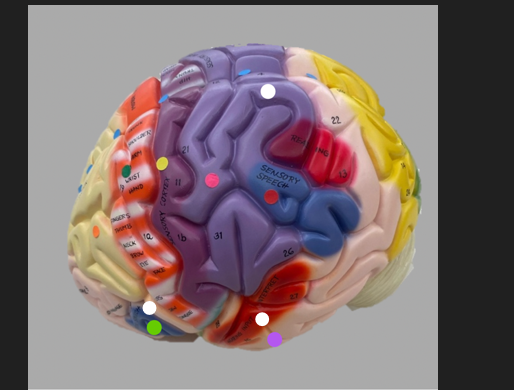

orange dot

frontal lobe

blue dot

longitudinal fissure

dark green dot

precentral gyrus

pink dot

postcentral gyrus

yellow dot

central sulcus

white dot

parietal lobe

light green dot

Broca’s Area

red dot

Wernicke’s Area

orange dot

occipital lobe

blue dot

parieto-occipital sulcus